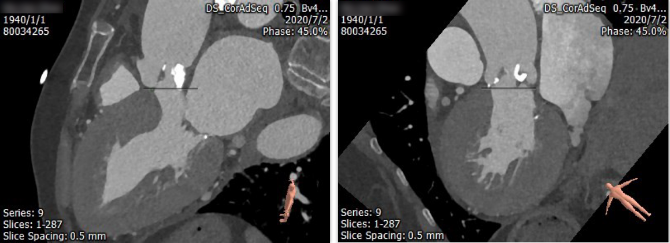

患者诊断为重度主动脉瓣狭窄合并中重度反流,考虑患者高龄,症状明显,心功能差,外科手术风险高,经心脏团队评估,拟行经皮导管主动脉瓣置入换术。

该患者左冠状动脉开口低,仅4.2mm,窦的结构不大,瓣叶较为冗长,冠脉堵闭风险极高,我院心脏团队对患者主动脉根部解剖结构细致分析以及充分风险评估后,制定了详尽的手术方案以及术后注意事项。在多学科相关医护人员的共同努力下,为该患者进行经皮导管主动脉瓣置入术治疗。术中采取了冠脉保护策略,更加有效的保障了患者的安全。手术顺利完成。患者1月后来我院随访,精神状态佳,活动自如,无头晕、气促、胸闷等不适,之前的心衰症状完全消失。复查心超提示心功能恢复良好,无明显瓣周漏,无明显跨瓣压差。